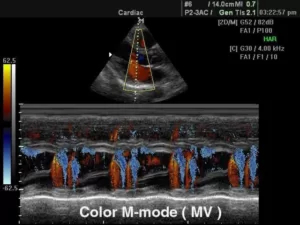

Существует несколько типов М-режима:

·      Color M-mode (цветной): сочетает стандартный режим и цветовое допплеровское картирование;

11.jpg